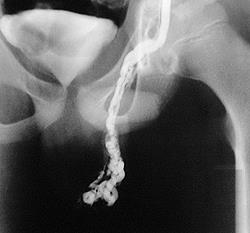

Забрюшинный подход (высокая перевязка, или операция Palomo) предполагает перевязку всего сосудистого пучка. Проводят разрез над внутренним паховым кольцом, и сосудистый пучок перевязывают в месте поворота сосуда. Таким образом, яичковую артерию также перевязывают. Кровоснабжение яичек обеспечивают артерии яичек и мышц, поднимающих яички. Лапароскопический доступ осуществляют чрезбрюшинно. Самый популярный консервативный подход — рентгенографическая эмболизация. Она представляет собой пункцию бедренной вены с проведением ангиографического зонда через полую вену, затем левую почечную вену в тестикулярную.

Рентгеноэндосакулярная окклюзия яичковой вены выполняется с использованием тромбирующих и склерозирующих препаратов, спирали Джанкуро. У опытного хирурга эмболизация, как правило, проходит столь же успешно, как хирургическое вмешательство. Данное оперативное вмешательство можно выполнить амбулаторно в условиях однодневного стационара.